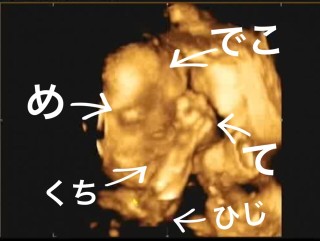

979g、少し大きめの男の子です。今回初めて4Dをして、あくびや指を吸ってる姿に感動!ですが、逆子だということも同時に分かり少しショック。。ともあれ、健やかに育てよ~!

4Dエコーだけの日でした。最初は私のお腹にぺったり張り付いていて下向きでした。。 半分諦めてたけど、エコー技師さんが頑張ってくれたおかげで一応記念に残る写真が撮れました!出産後この写真とどのくらい似てるか気になるところです!